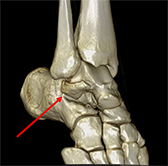

X-rays and CT scans not only confirm the diagnosis, but help determine the treatment course. The piece(s) of bone that breaks off the lateral process of the talus can vary in size and number. The pieces that break away can either be shifted away from their normal position (displaced) or remain in place (non-displaced). As the fracture can involve the articular surfaces of the ankle and subtalar joint, it is important to start appropriate treatment promptly to avoid further degeneration of the joint.

Many lateral process fractures of the talus are displaced or unstable enough to require surgical fixation. If the displacement is more than 2mm, an open reduction and internal fixation may be performed. This involves an incision on the lateral aspect of the ankle, through which lag screws or wires are used to stabilise the bone fragment to the talus body. If there are any loose bodies found during the surgery, these are also removed.

Sometimes the bone will be broken into multiple pieces (comminuted) that are non-viable. In this case, it may be necessary to excise these bone fragments from the ankle.